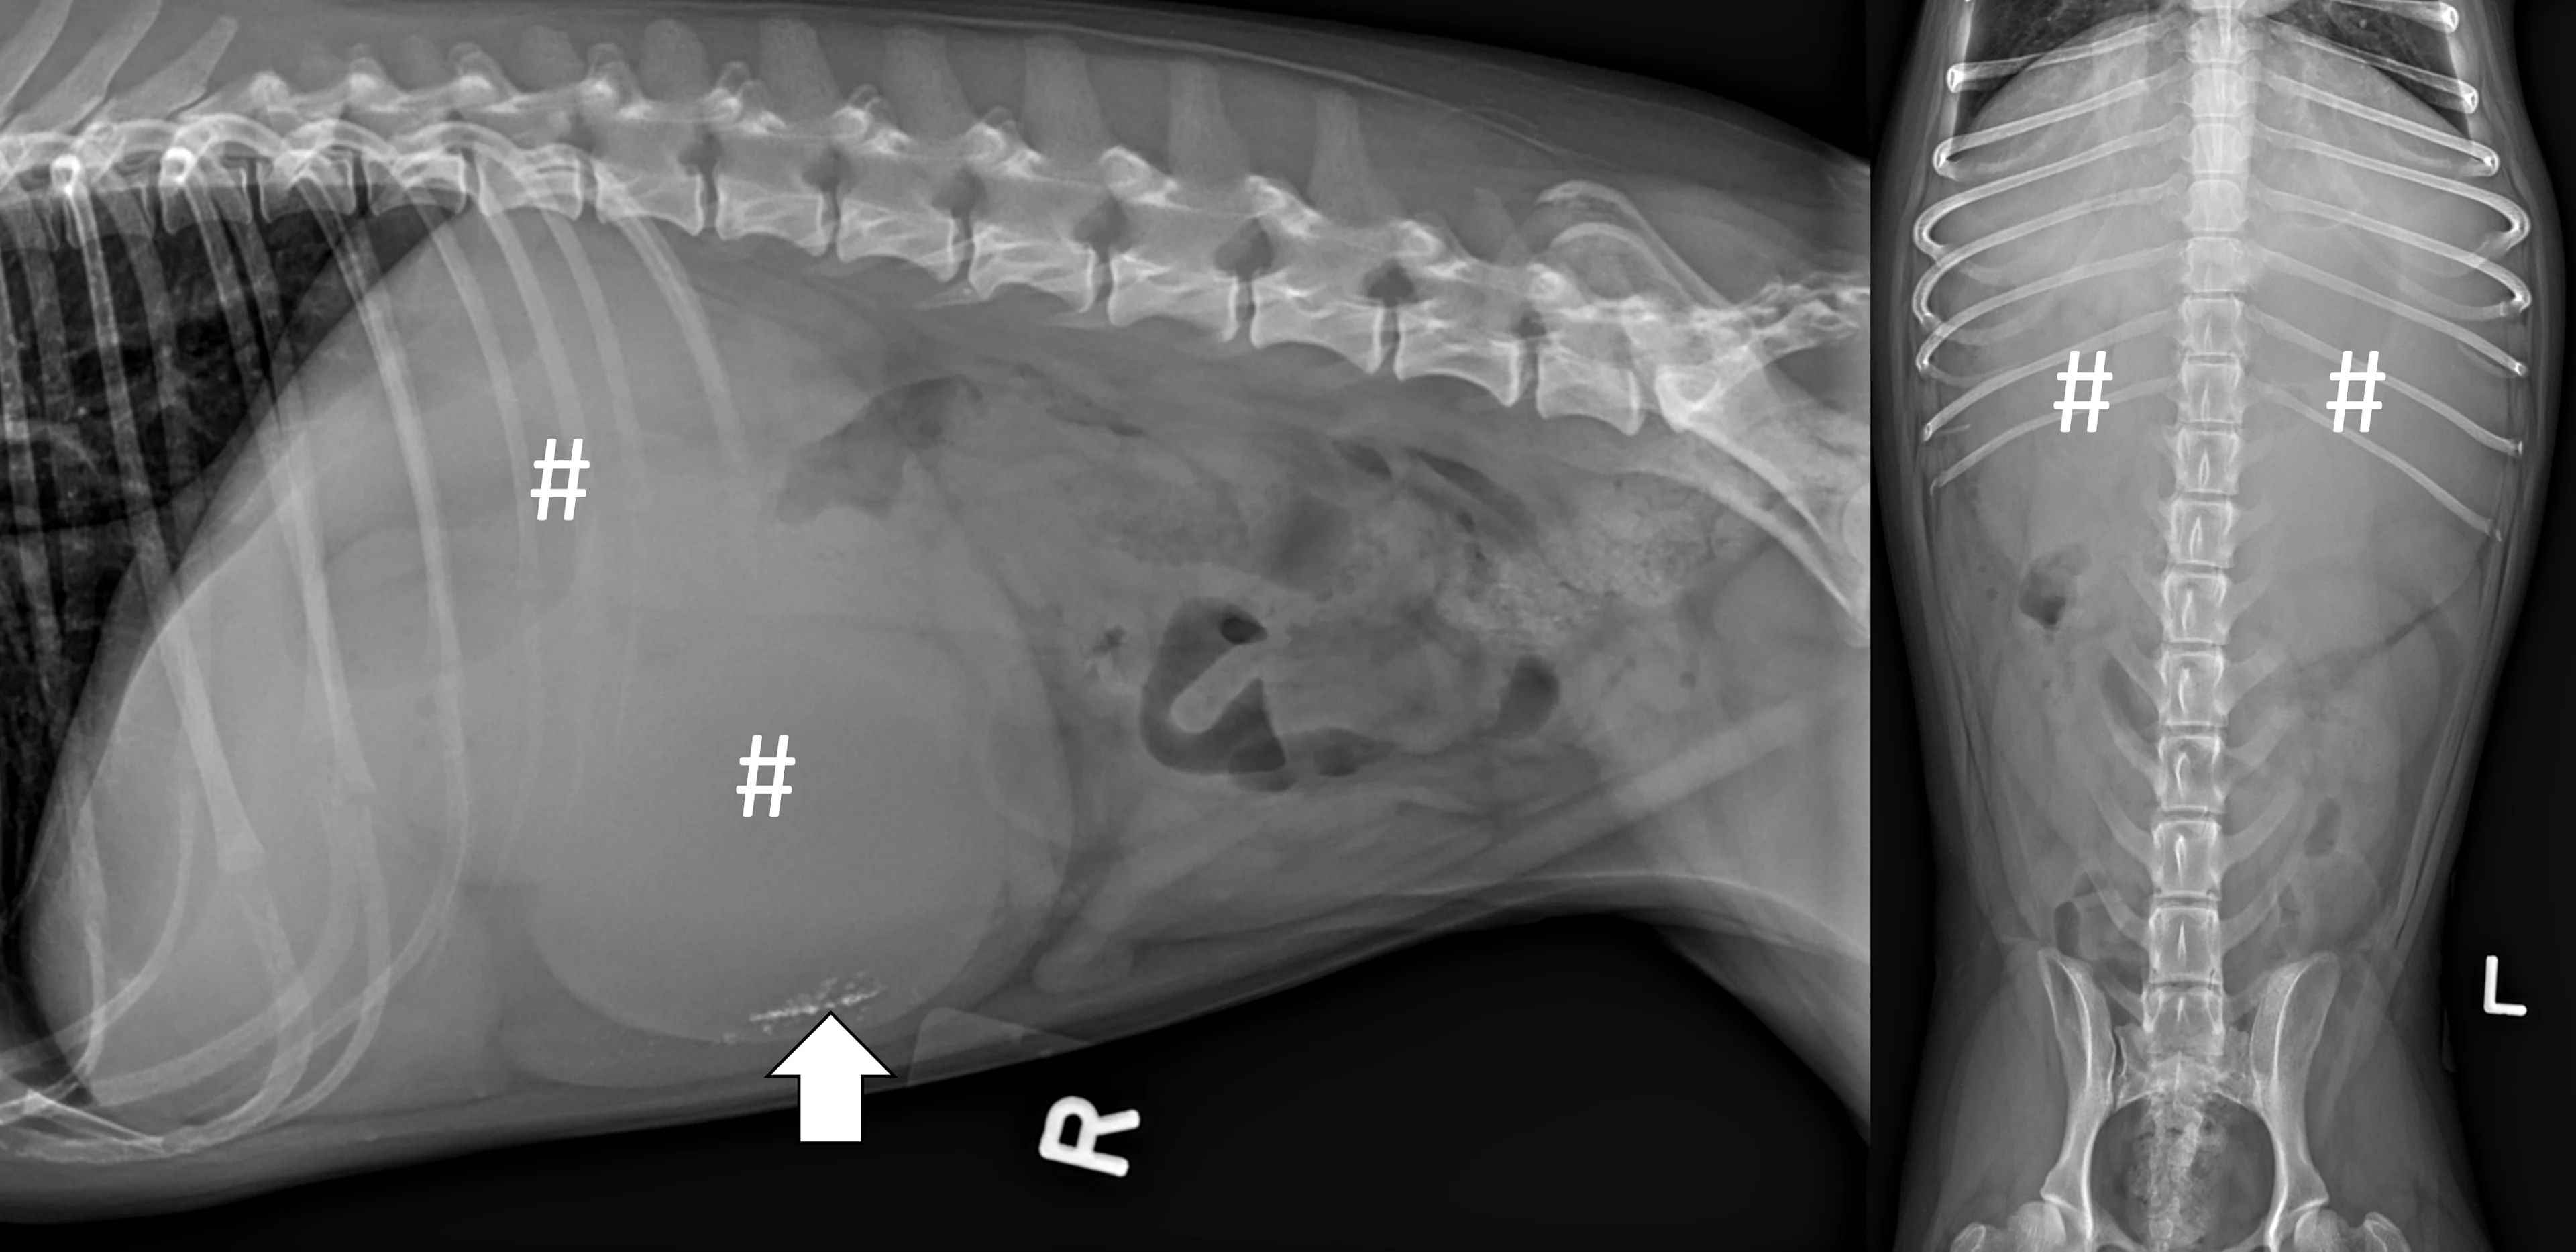

Evaluate the peritoneal space for decreased serosal detail and/or free gas, the combination of which strongly suggests septic peritonitis secondary to GI perforation (Figure 2).

Right lateral and ventrodorsal abdominal radiographs of a 10-month-old neutered male pit bull with a small intestinal mechanical obstruction of undetermined etiology. The stomach is moderately dilated with fluid and gas (pound signs), and there is moderate segmental dilation of the small bowel with stacking and hairpin turns (asterisks). Peritoneal serosal detail is diffusely decreased with a small, tear-drop–shaped intraperitoneal gas bubble between the liver and stomach (arrow) consistent with septic peritonitis secondary to presumed GI perforation.